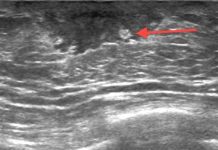

Ведущую роль в верификации диагноза и оценке тяжести процесса играет рентгенодиагностика, начинающаяся с обзорной рентгенографии брюшной полости. На снимках при остром воспалении визуализируется увеличение почки, нечеткость её контуров и исчезновение тени поясничной мышцы из-за отека клетчатки. Основным функциональным методом служит экскреторная урография, позволяющая оценить динамику выведения контраста. К рентгенологическим признакам острого процесса относятся замедление выделения вещества, ограничение подвижности почки при дыхании и спастическое сужение чашечек. При хроническом течении рентгенодиагностика выявляет деформацию чашечно-лоханочного комплекса, булавовидное расширение чашечек и симптом Ходсона — локальное истончение паренхимы. Лечение носит комплексный характер и базируется на назначении антибактериальных препаратов (цефалоспоринов или фторхинолонов) для подавления возбудителя. Обязательным условием является обеспечение оттока мочи, что контролируется рентгенологически при наличии препятствий. Скрининг пациентов с хронической формой направлен на выявление сморщивания почки через контрольные снимки. Профилактика заключается в устранении уродинамических нарушений и поддержании достаточного диуреза.